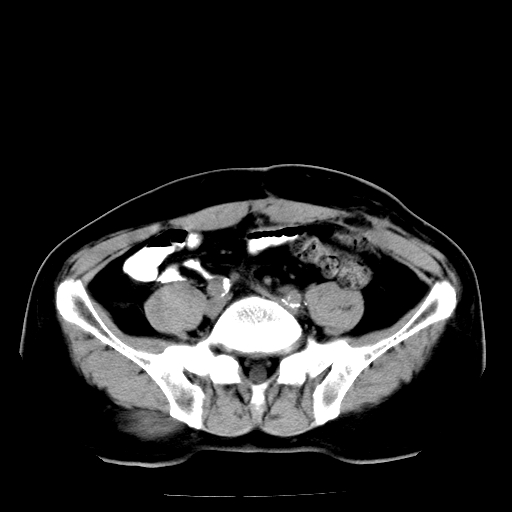

男,66岁,直肠癌术后一个月,化疗前ct检查。

膀胱充盈不太好,前列腺较大,前列腺肥大?占位?建议:结合临床.

直肠癌造瘘术后改变,周围淋巴结转移

直肠癌造瘘术后改变,盆腔多发淋巴结转移

直肠壁厚,盆腔多发淋巴结转移.

直肠癌造瘘术后改变,直肠周围软组织增厚,盆腔多发淋巴结转移。前列腺肥大。

盆腔内有很多点点,可能是淋巴结转移,建议增强。“直肠周围浸润”无法与术后斑痕鉴别,治疗后再说